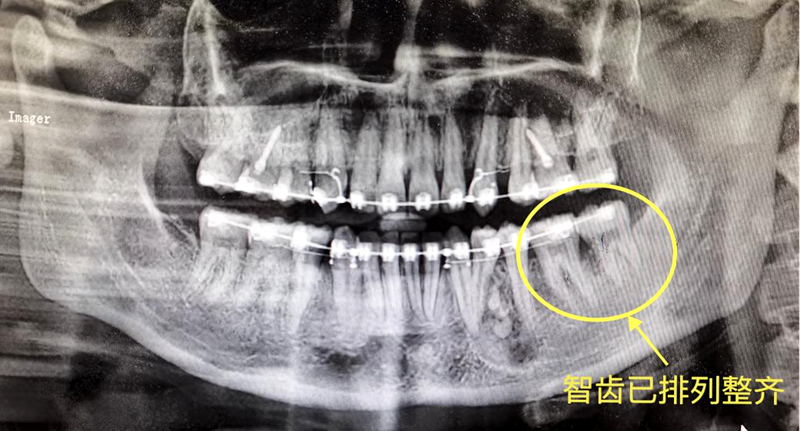

以下为口腔门诊部治疗案例展示:患者姚女士左下第一磨牙因为严重龋齿而拔除,左下智齿倾斜,但牙体无龋坏,牙周情况良好,加上患者牙齿不齐,有矫正牙齿的意愿,经过医生充分评估和沟通后开始了正畸治疗。经过正畸治疗,患者不仅左下智齿逐渐排齐,恢复正常咬合,原来磨牙缺失造成的间隙得以关闭,还收获了整齐的牙列。

(患者治疗中牙片)